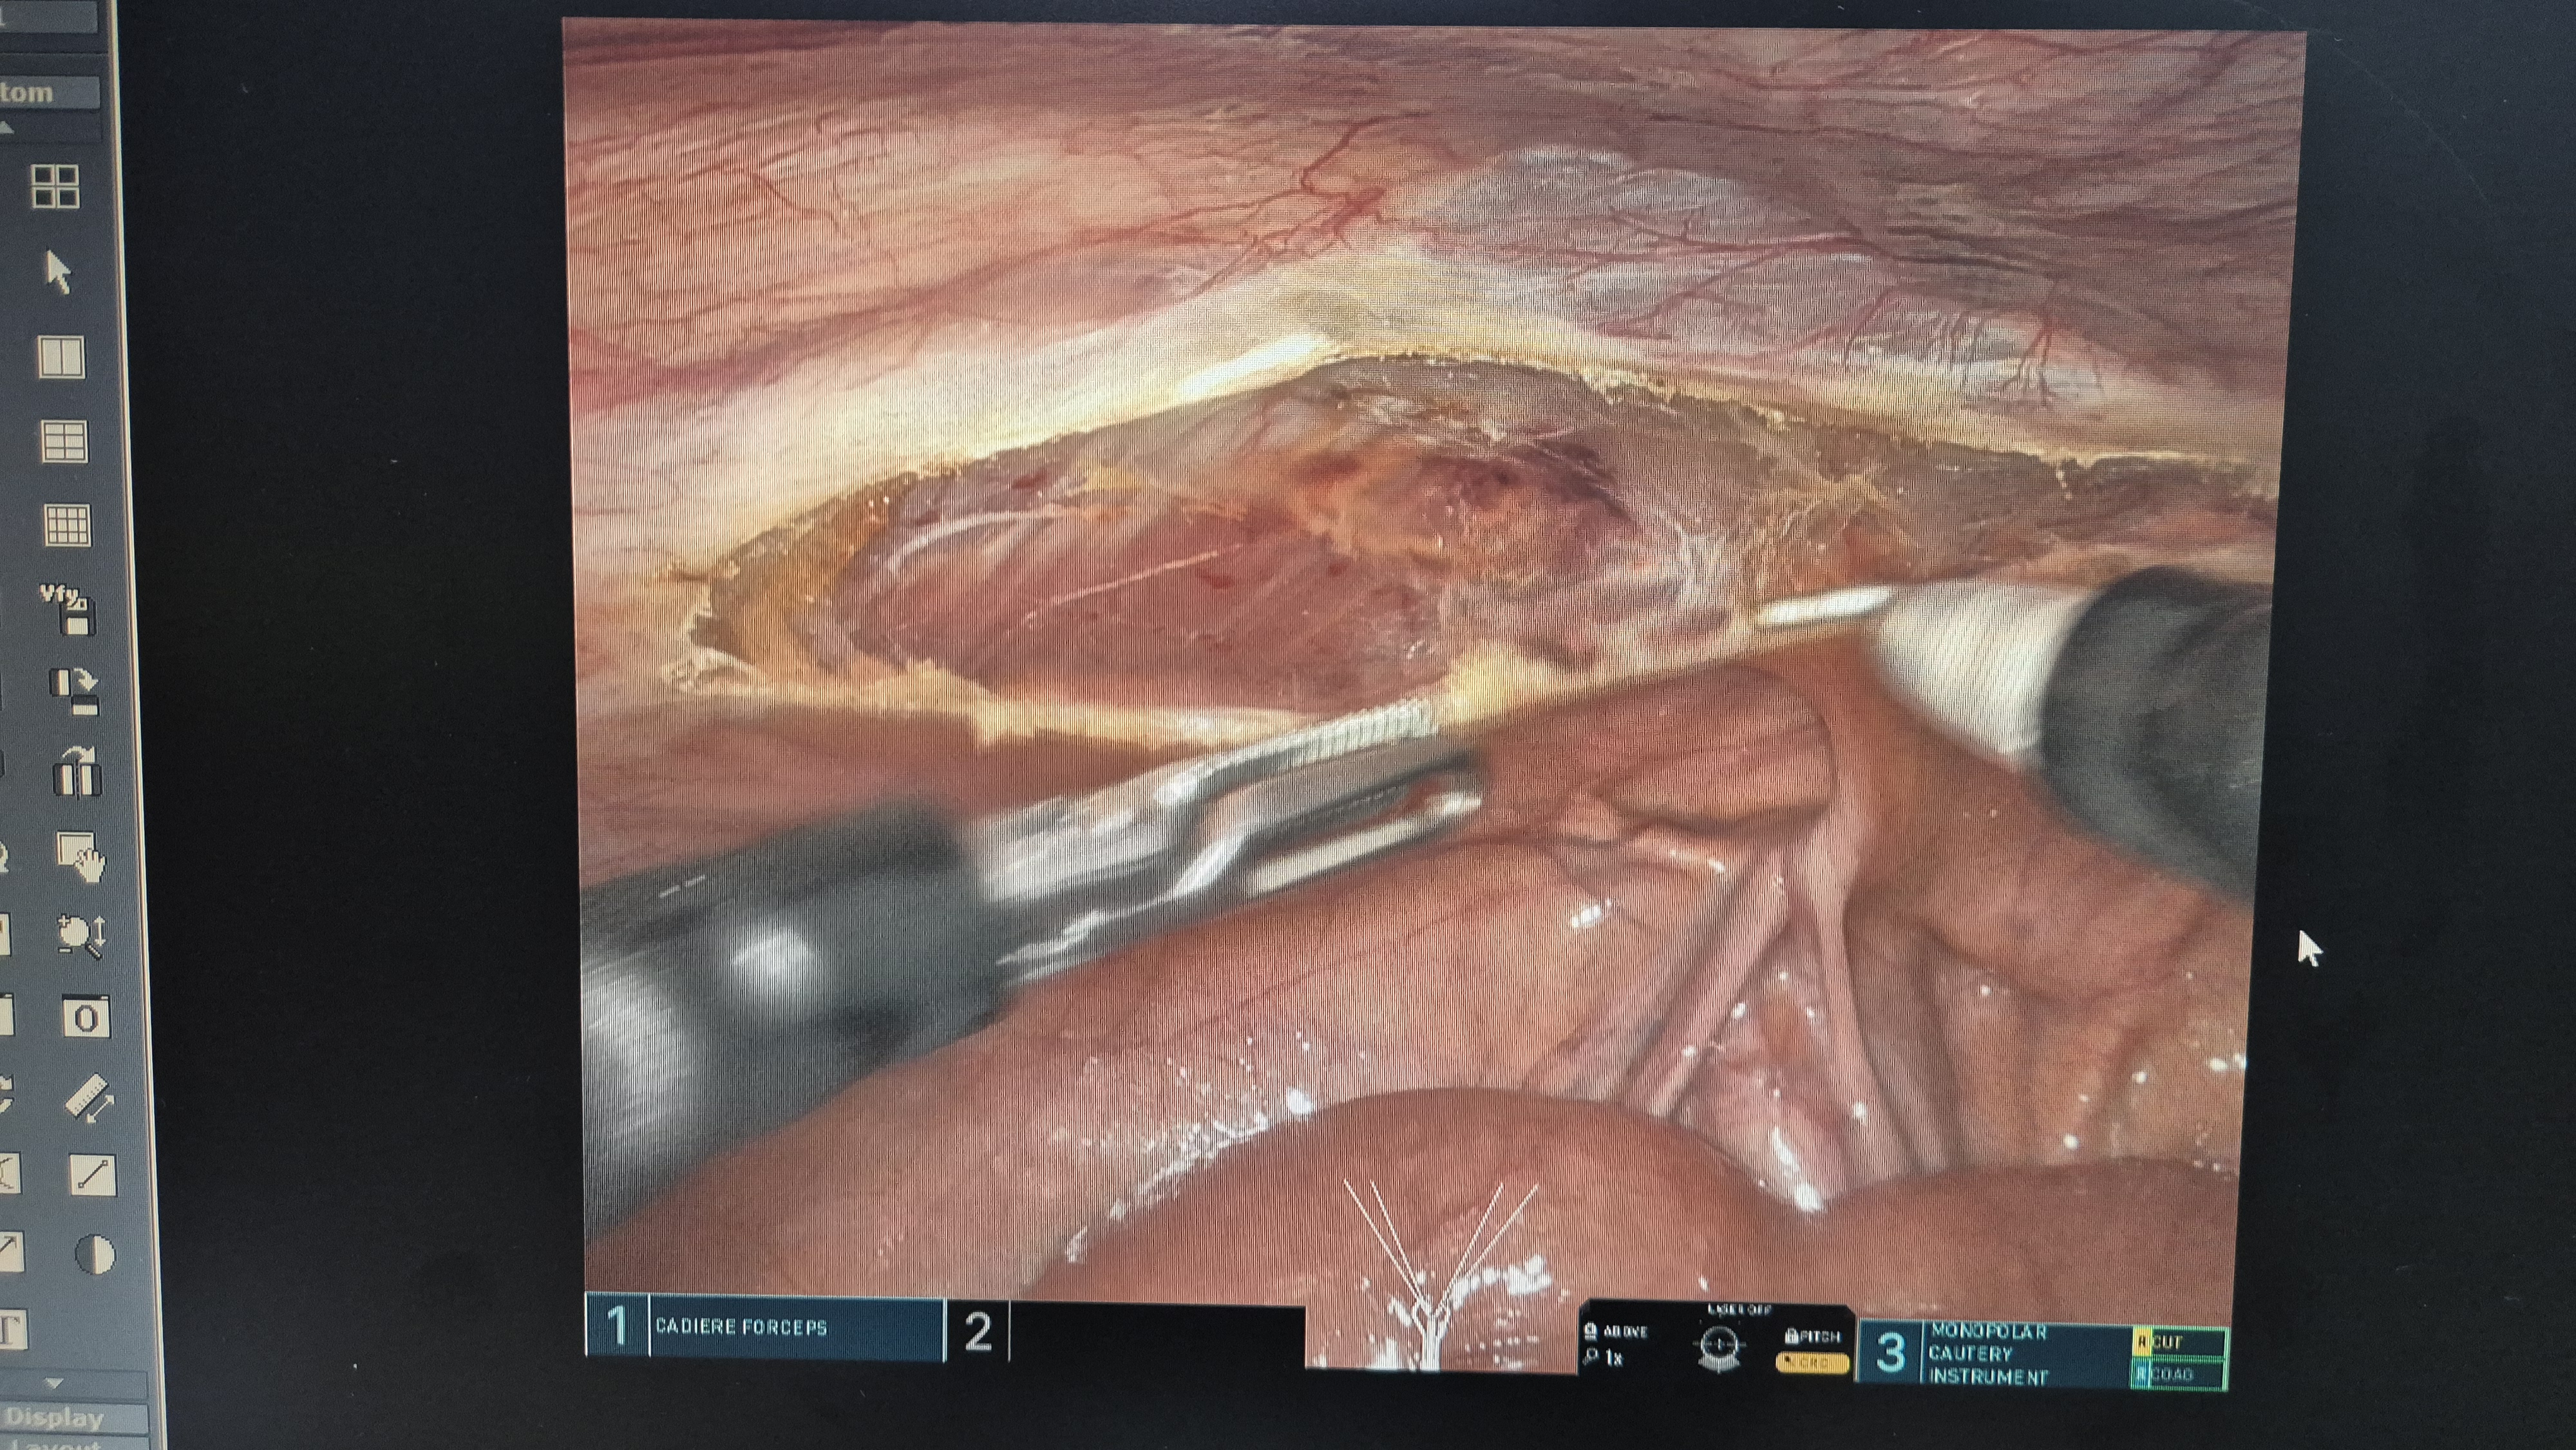

우측 서혜부 탈장.

복막을 열고.